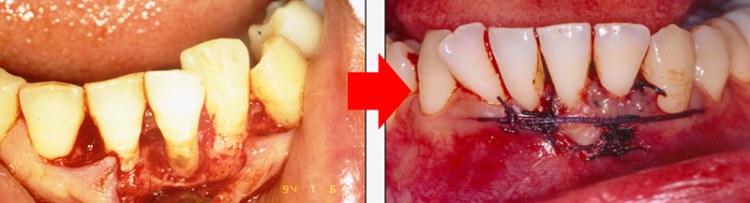

그러나 기존의 치료 방법들은 메스로 잇몸을 절개를 해서 수기구로 치석을 제거하는 방식이라 통증과 회복 기간도 상당하게 발생하는데

더 위험한 것은 잇몸뼈가 공기 중에 노출되면 뼈가 녹는 속도가 훨씬 빠르고 잇몸이 약해지기 때문에 좋은 결과를 기대하기는 어렵습니다. 3232235521_UMJFRCEv_1ae2fad53fafee3cb764ae2ee81e54d4db3ad922.png 그렇다면 잇몸 속 치석을 방치하고 잇몸 내려앉음이 발생하는데도 손 놓고 기다려야 하는지 마음이 안 좋으실 텐데요. 3232235521_IaTqZzGP_4055b8d6ace5f5edbe40d099fe24107132a7aa88.png